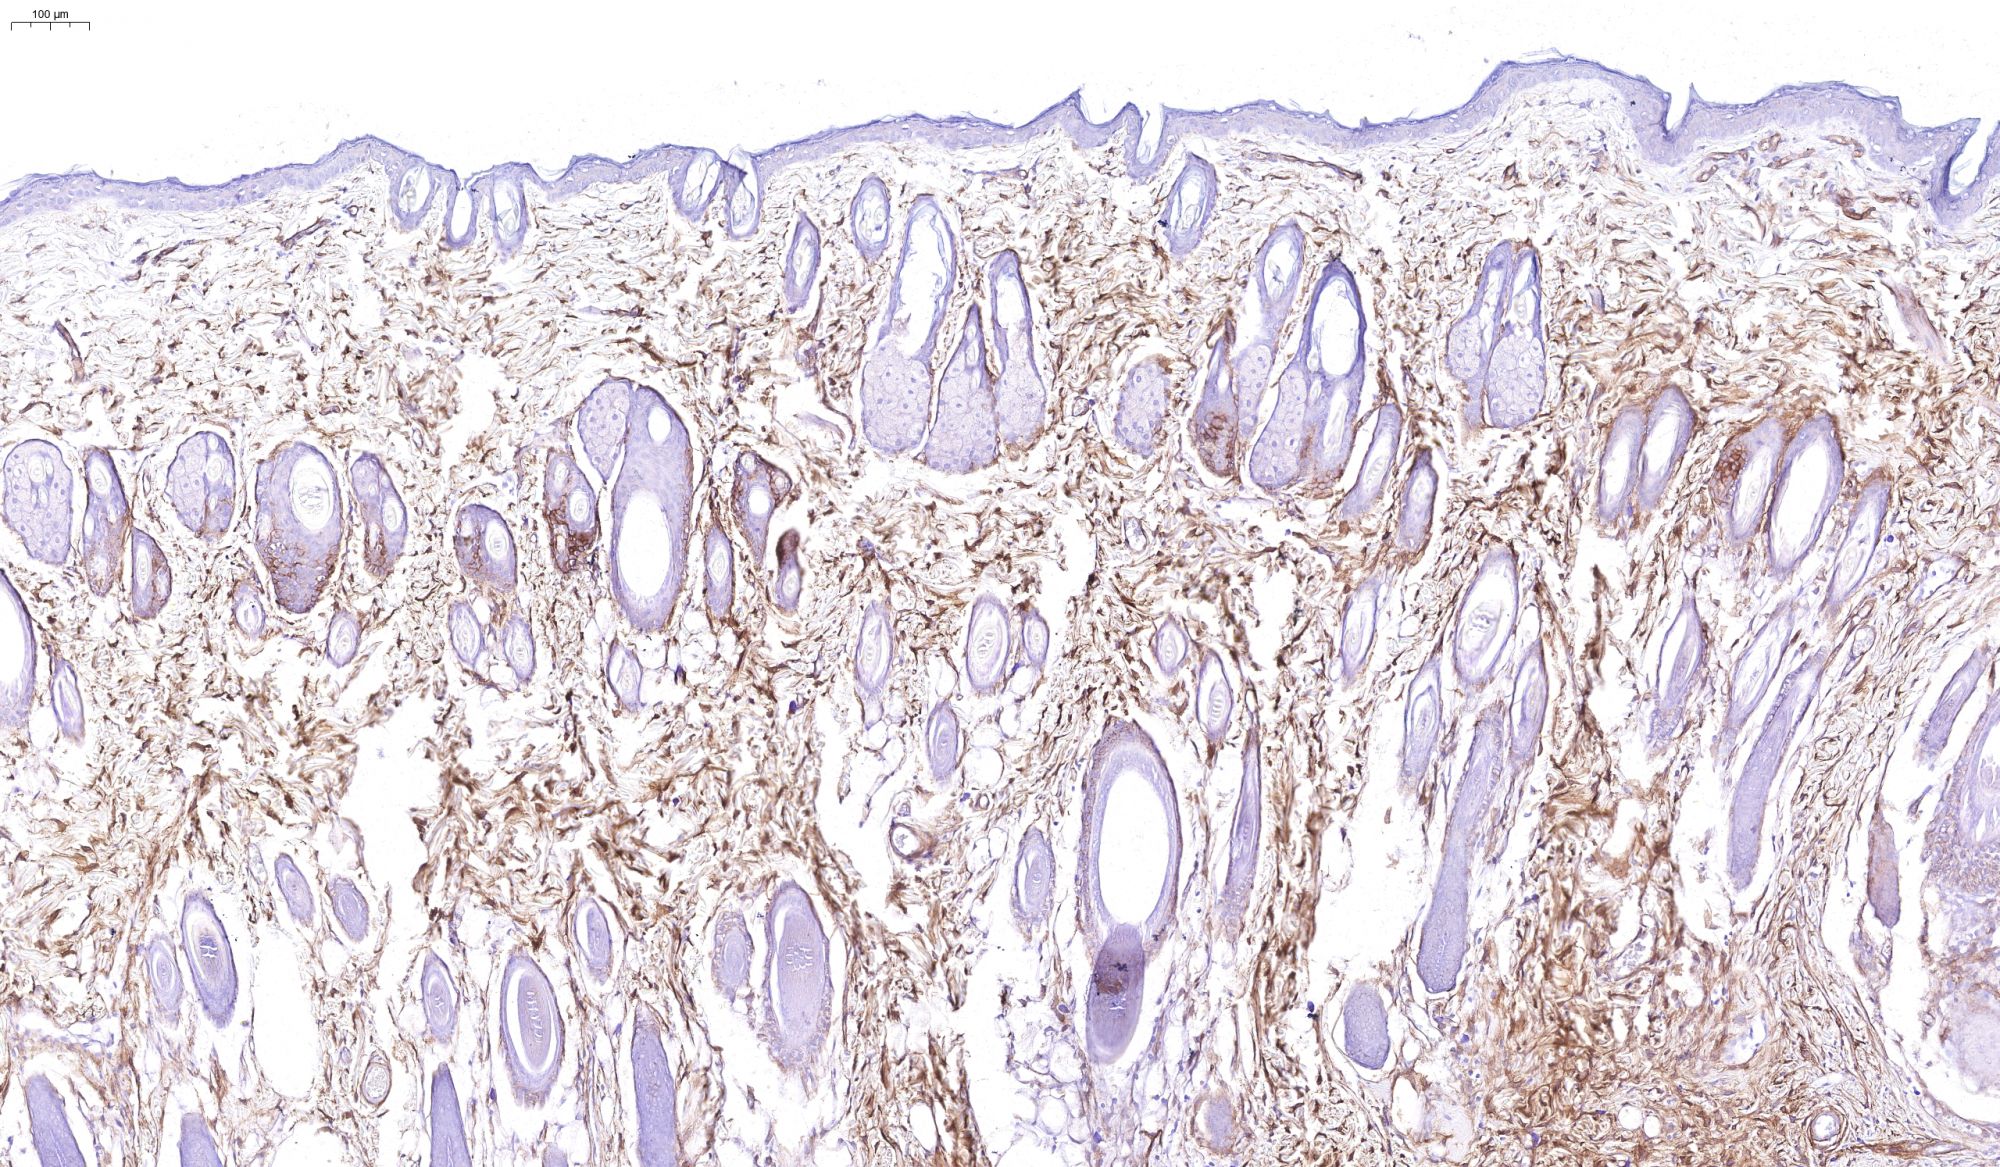

優(yōu)秀案例(免疫組化)